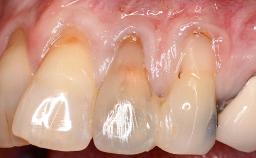

Implant Placement in the Esthetic Zone and Coverage of Multiple Gingival Recessions

This case illustrates use of a modified ‘tunnel’ technique, which has been shown to be highly effective in root coverage procedures. The tunnel technique is used to achieve soft-tissue augmentation across the anterior area, including the planned implant site, using collagen matrix as grafting material. The patient is a 47-year-old woman with high esthetic expectations. Her main concern was the appearance of the anterior teeth and their “elongation”.